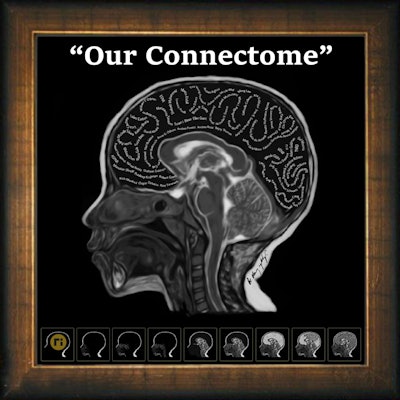

Art and radiology may seem like very different fields, but they can intersect in intriguing ways, particularly in medical imaging and the visualization of complex clinical data. Dr. Harun Yildiz has a keen interest in pediatric radiology, including ultrasound. All images provided by Dr. Harun Yildiz.

Dr. Harun Yildiz has a keen interest in pediatric radiology, including ultrasound. All images provided by Dr. Harun Yildiz.

Conceptually, I think it is possible to define the term “radiological illustration” as an emerging discipline that transforms medical imaging data into an aesthetic and didactic narrative. I emphasize that with the motto “pixel by pixel handmade.” I am trying to open a “new path” for the use of visual communication in medical education by trying to combine scientific accuracy in radiological terms with artistic creativity. With this statement, I am trying to express that instead of modifying radiological images, I draw each pixel by hand using technological tools and create a new visual that is both artistically and scientifically original, while remaining faithful to radiological principles.

It’s important to note that radiological illustration should not be confused with medical illustration. The former has yet to be systematically defined in the literature. I believe it deserves recognition as a distinct sub-branch within the broader medical illustration domain.